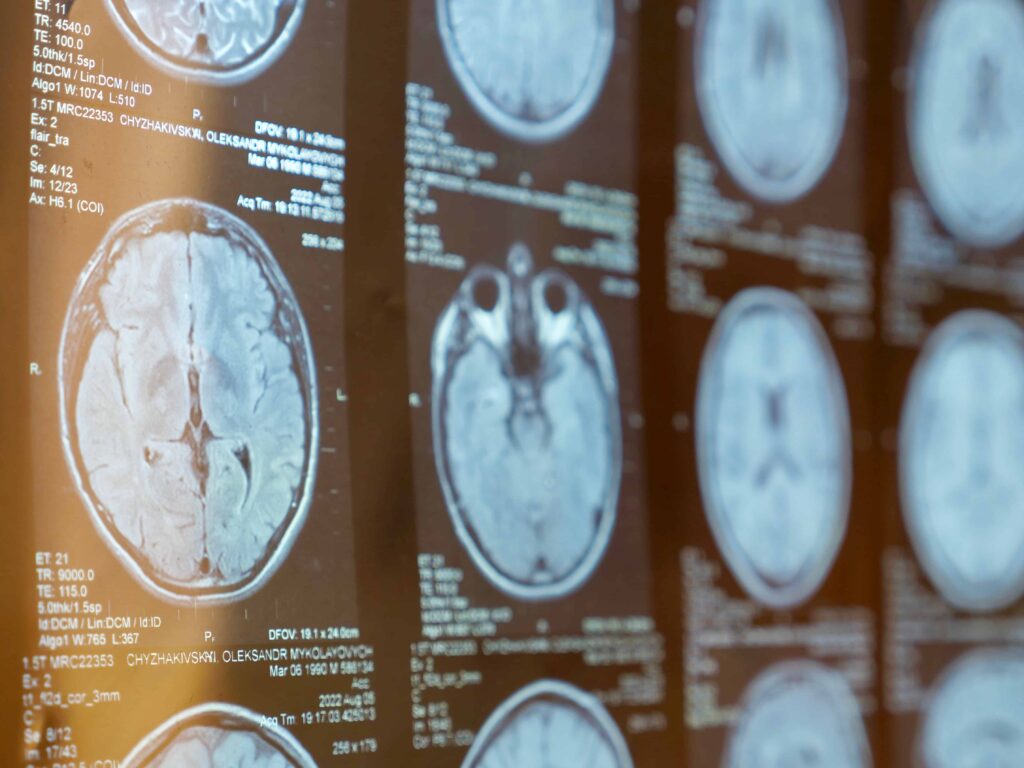

Many people with concussions look fine on the outside. Imaging tests like CT scans or MRIs often come back normal because they aren't designed to detect the cellular or chemical changes happening inside the brain. Yet, the damage is real, and it can affect everything from relationships to employment.